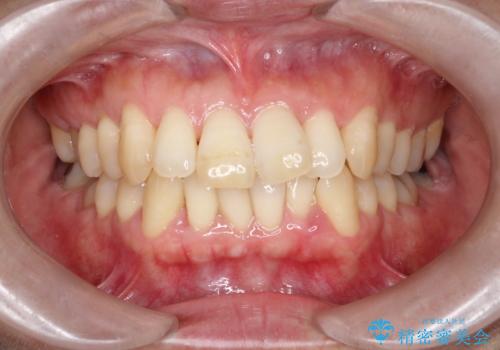

前歯が前に出ていることや歯並びの凸凹が気になるという主訴でした。十分なスペースを確保するため上下左右の第一小臼歯(4番)を抜歯し、そこに前歯を移動させて整列を行いました。矯正装置には目立ちにくい透明なブラケットを選択し、見た目のストレスを軽減。矯正期間中は定期的な通院でワイヤーを微調整し、無理なく確実に歯を動かしました。治療後は前歯が自然な位置に下がり、口元の突出感が解消されるとともに、美しく整った口元に仕上がり、患者様にも大変喜んでいただけました。